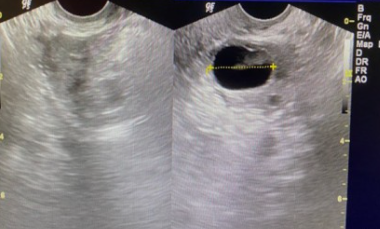

3) 초음파 검사 확인법

초음파로 난포의 크기를 측정하면 배란일을 예측할 수 있습니다.

난포는 배란 전까지 일정한 크기로 자라다가 배란 직전에 20~25mm로 성장합니다.

생리주기가 규칙적이지 않아도 초음파로 난포의 크기를 측정하여 배란일을 예측할 수 있습니다.